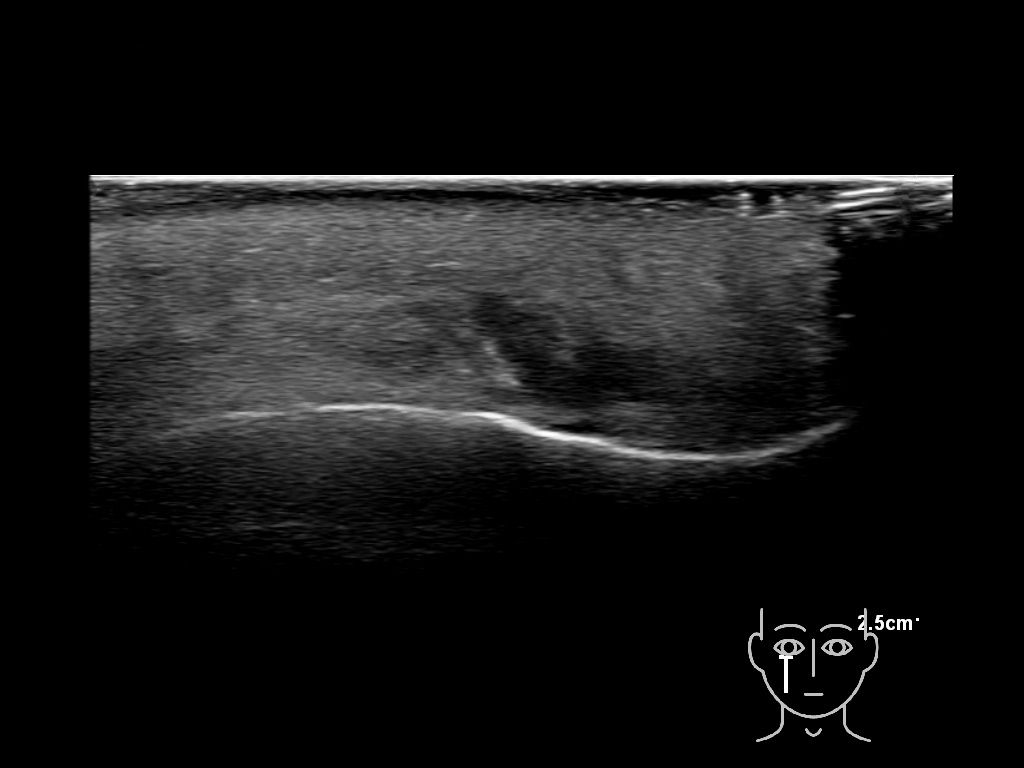

With ultrasound signs of inflammation can be visualized. Edema can be seen as a hyperechoic appearance of the subcutaneous fat, sometimes separated by hypoechoic fluid filled area’s, known as cobblestone appearance. Increased vascularization (hypervascularity) can be seen on colour Doppler. An abscess will appear as a fluid collection appearing as an irregular hypoechoic area with heterogeneous internal echoes and a thickened wall. Posterior acoustic enhancement can be present, and there is vascularity around but not within the mass. Under ultrasound guidance, abscesses can be managed by needle aspirations (18G) under antibiotic cover.

Study the first image to recognize the different layers. If you are sure about the layers, swipe to the second image to view the answer (if applicable).